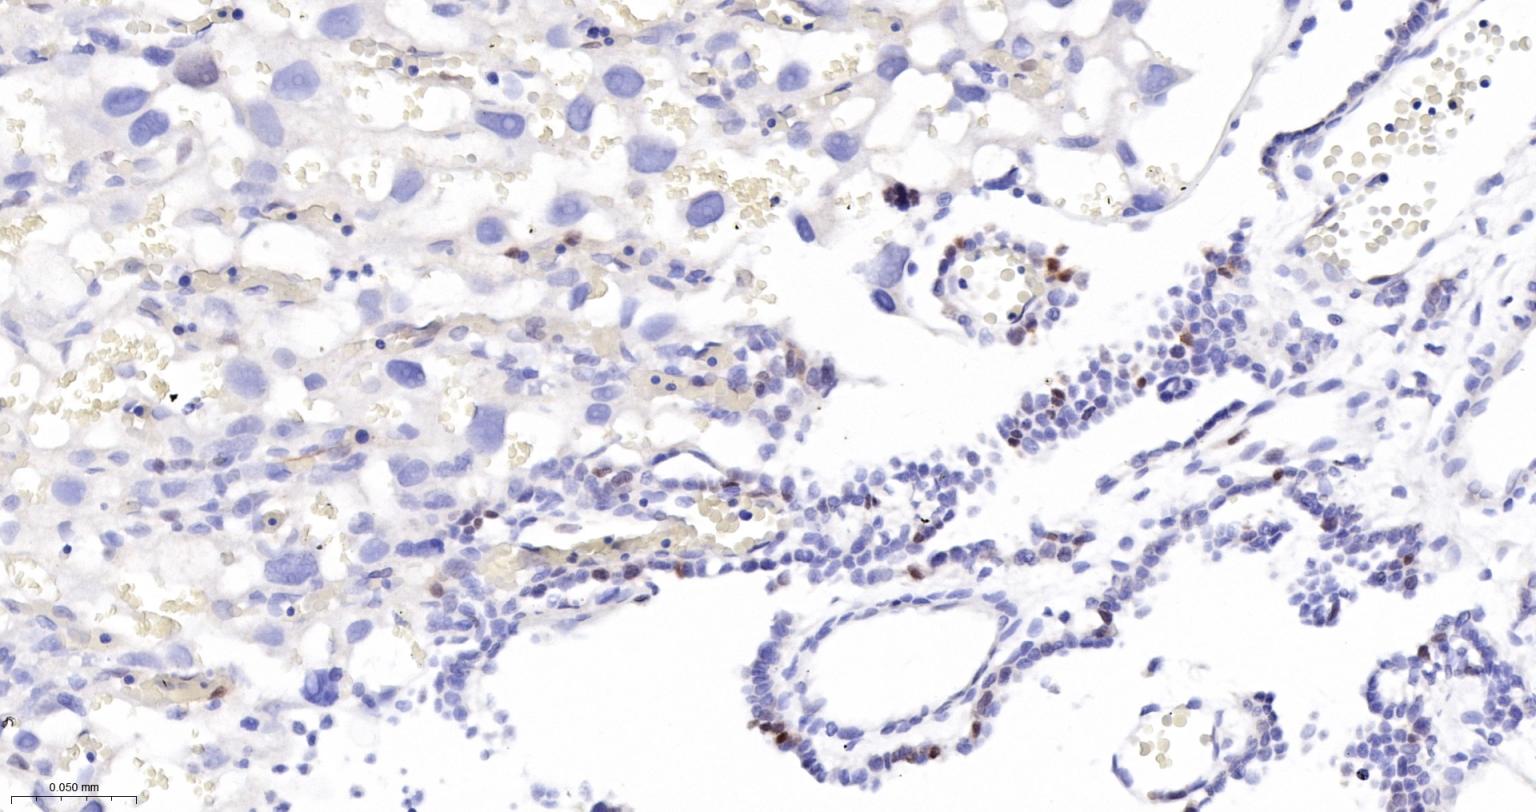

Paraformaldehyde-fixed, paraffin embedded Rat Small Intestine; Antigen retrieval by boiling in sodium citrate buffer (pH6.0) for 15 min; The section was incubated with Survivin Monoclonal Antibody, Unconjugated (bsm-54475R) at 1:200 overnight at 4°C, followed by conjugation to the bs-0295G-HRP and DAB (C-0010) staining.